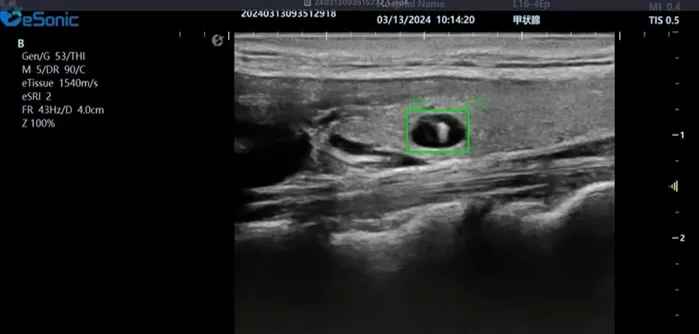

3377体育医疗(ESI)表示,其最新的人工智能功能可以帮助到医疗机构的工作效率,功能包括,实时、动态、快速自动识别病灶,良恶性病灶概率预测,甲状腺结节和乳腺的二维灰阶动态自动实时检测需求,提供多个结节动态检测轮廓框。实时获取多幅具备临床特征(大小、属性等)的结节切面,同时提供当前切面所示结节的结节大小、属性特征、TI-RADS 分级。

对于甲状腺结节相关的自动检测功能,甲状腺结节病灶检出率≥95%,良恶性分类灵敏度≥90%、良恶性分类特异度≥85%。